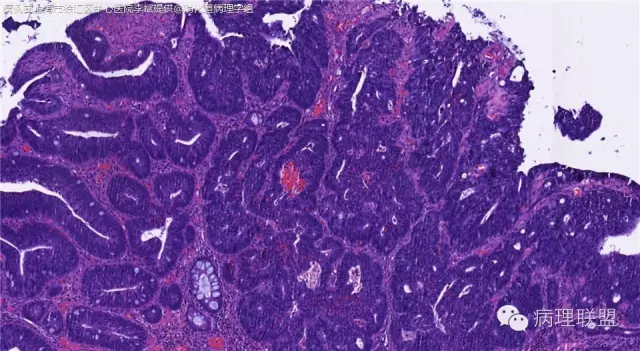

男,72岁,距肛门口30cm息肉。大体:灰白结节1.5*1*0.8cm拟发管状腺瘤并部分区高级别,请各位老师指导!(病例由上海市徐汇区中心医院 李斌 提供,致谢!)

这一例有两种不同看法,按WHO标准,为高级别,按实际工作,要发粘膜内癌。WHO第三版与第四版均提出,侵犯至粘膜下层才能诊断为癌,声称结直肠粘膜内没有淋巴管,发生转移的概率较小,但是粘膜内有血管,肿瘤侵出粘膜腺体基膜以外,就能侵犯血管,照样可以发生血道转移。文献报告与我们的工作实践,发现腺瘤、高级别(没有侵出基膜)的患者,同样有发生血道转移。因此,我们废弃了这一条WHO标准(不是所有的WHO标准都是一定要执行的)。只要异型增生腺体呈毛刺状、迷芽状侵出粘膜腺体基膜,位于粘膜肌层以内,就发粘膜内癌。

@李斌 结肠腺瘤这例我认为已经有黏膜下浸润了,因为有些腺体间的间质已经不是固有膜间质而是促结缔组织增生反应的间质了。但即使有浸润癌,如果息肉完整摘除、癌成分分化好、没有脉管瘤栓、浸润癌距切缘大于1mm(日本标准还要看浸润癌超出黏膜肌深度和肿瘤出芽情况),也不需要进一步治疗。所以,对于这类可能存在争议的病变,特别是息肉已经完整切除的病例,诊断的关注点就应该放在寻找需不需要进一步治疗的证据上了。@邓永键 2010版WHO在腺瘤部分的陈述中已经写出对于有局灶浸润性生长的病例也可以称黏膜内癌,他们在悄悄的让步。